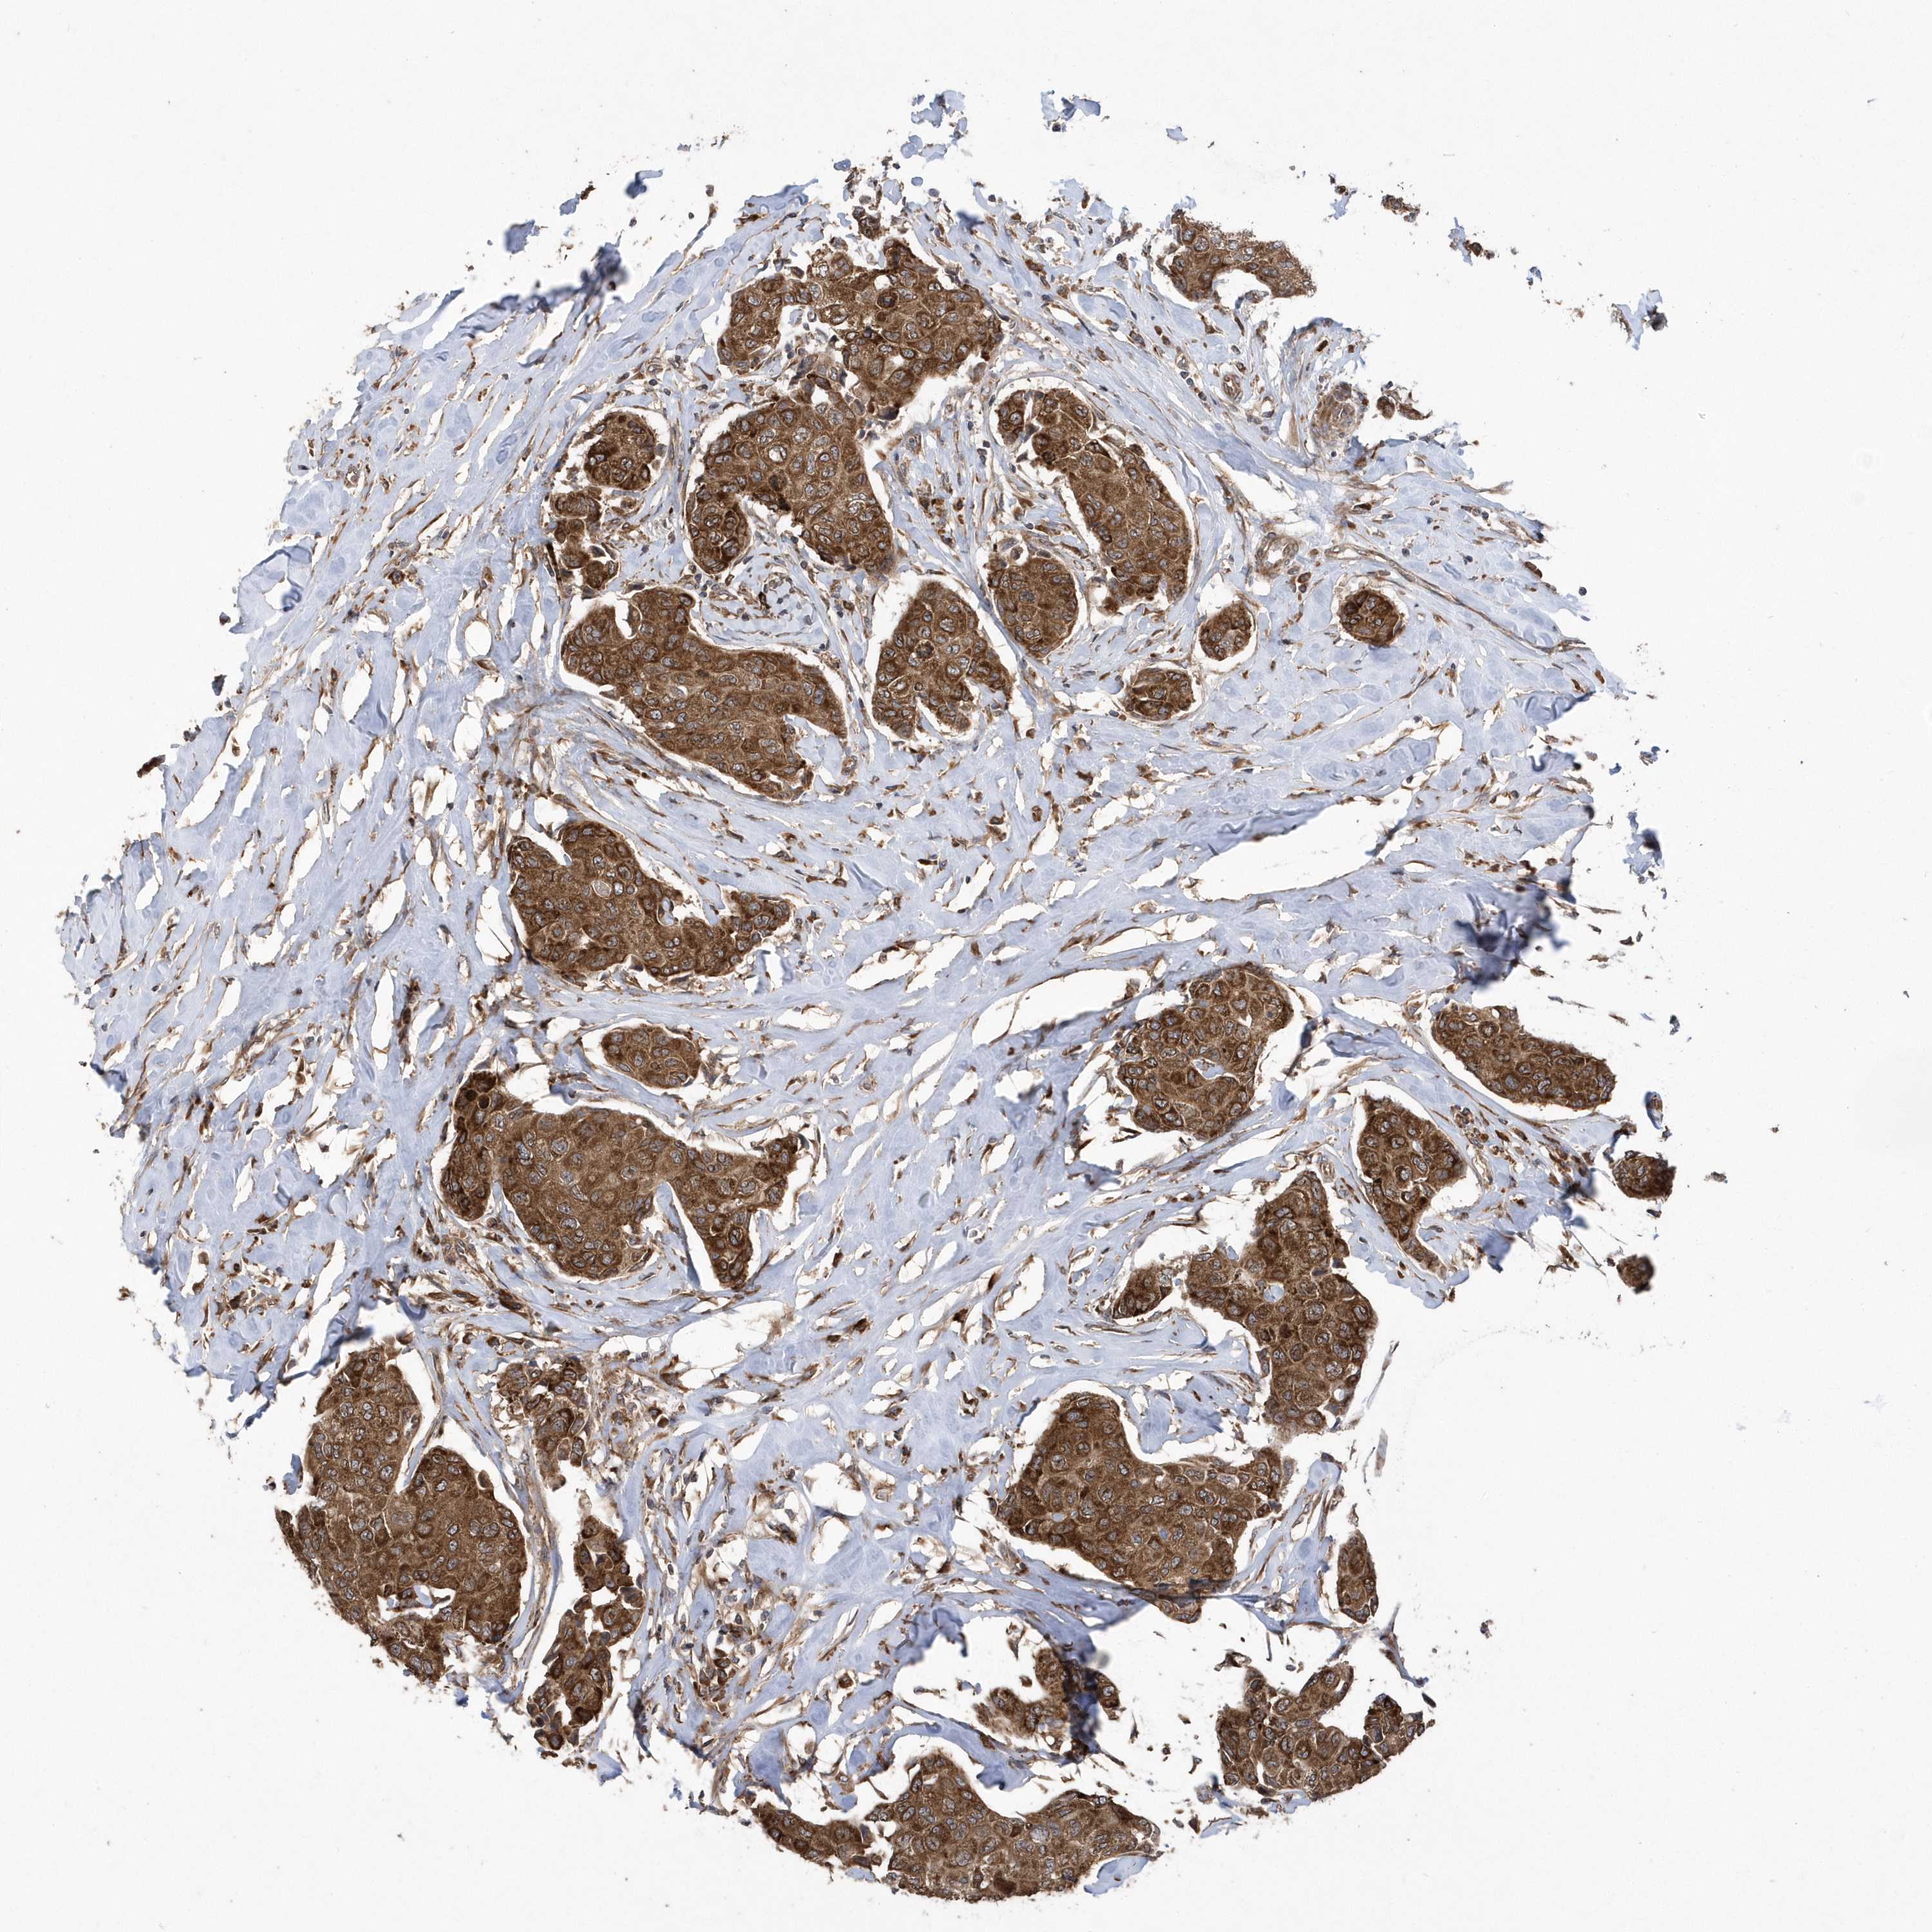

CANCER BREAST CANCER Show tissue menu

BRCA TCGA BRCA VALIDATION PROTEIN EXPRESSION